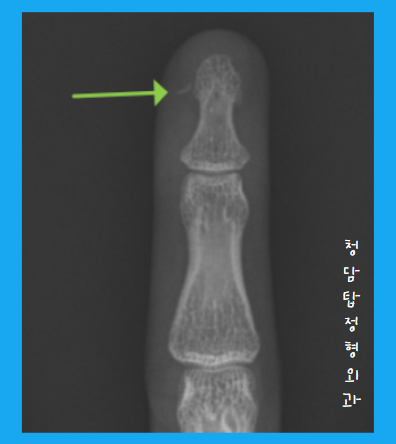

이 과정이 끝나면, 다시 엑스레이를 찍어 제거가 여부를 다시 확인을 합니다.

찍어보니, 숨어있던 파편이 보이네....요??

다시 시작해 볼까요?

진짜 마지막으로 엑스레이 다시 찍어볼게요!

이제 진짜 깨끗하게 제거가 됐습니다.